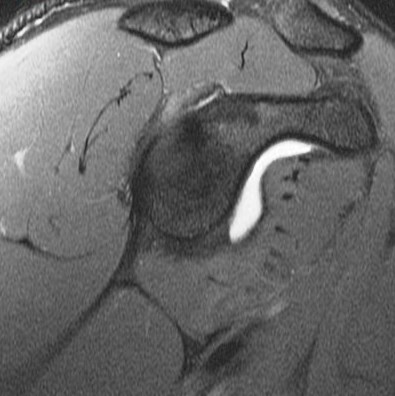

19 y/o college pitcher. Pain with throwing.

Posterior superior glenoid bone build up from chronic peel back stress. There are superimposed acute edematous changes. Abstract from Burkarts article describing it is included. Reference article.

Posterior Peel Back Lesion of Internal Impingement